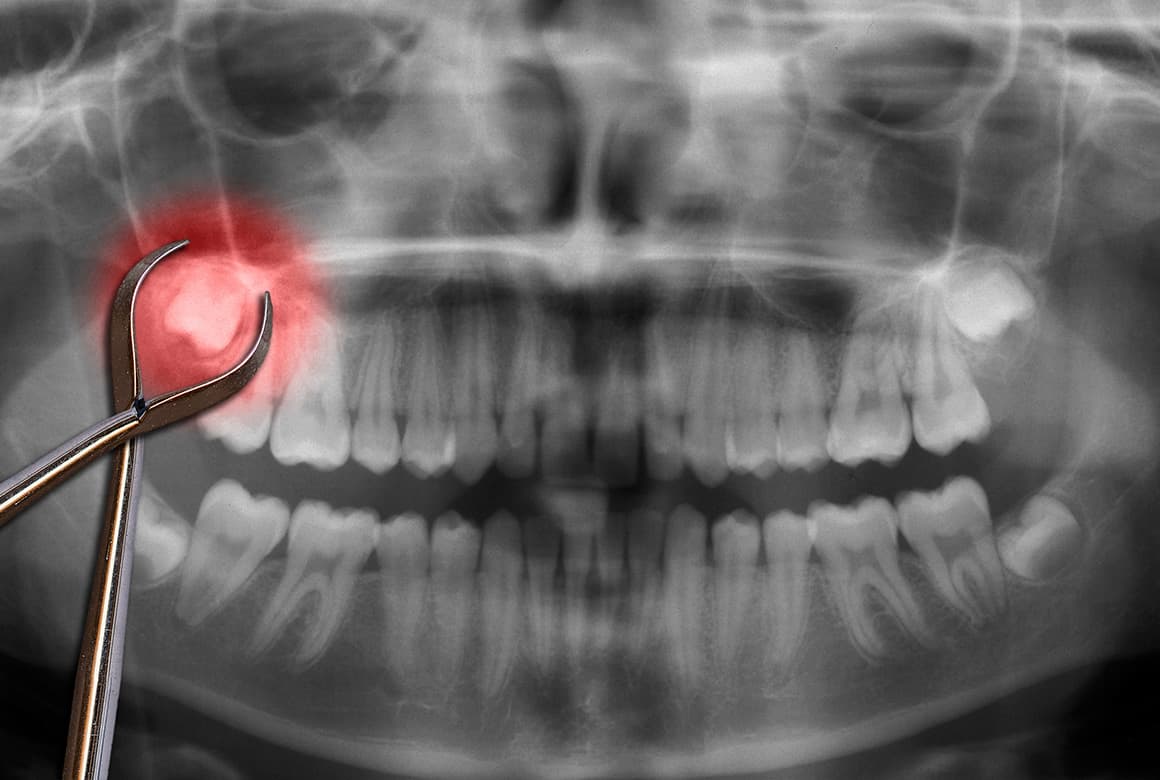

親知らずの抜歯後には、神経麻痺や後出血ほか合併症などのリスクがあるのが事実です。それらを防止するため、当院では親知らずがどのように生えているかを確かめる事前のCT撮影による精密検査を怠りません。

その後、検査結果をもとに現在の状態や抜歯の必要性などを丁寧にご説明。患者さんにご納得いただいてから、治療に入ります。